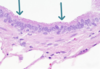

Name the following tissure.

Endothelium

- simple squamous epithelium.

Name the following picture.

Ovarian surface

- simple cuboidal epithelium.